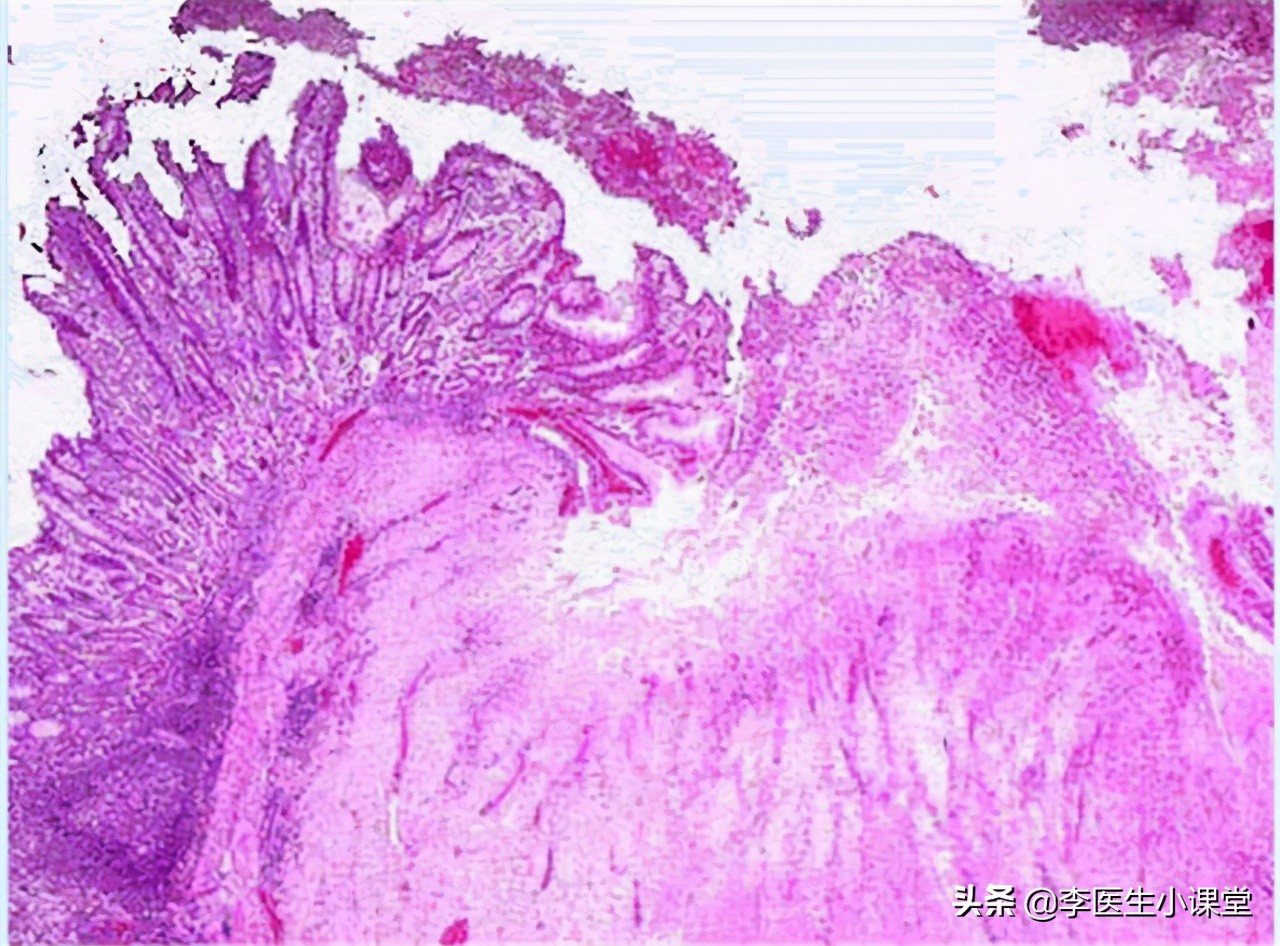

浅表性胃炎 ,又称为 慢性浅表性胃炎 ,是一种很常见的慢性胃炎。是在相关的致病因素作用下,胃黏膜发生以淋巴细胞浸润为主的,可能伴有糜烂、胆汁反流的慢性炎症。

其实临床上,大多数人去做胃镜,都会检查出有慢性浅表性胃炎。而其中有一部分原因,是功能性消化不良或者是非溃疡性的消化不良,并不是胃黏膜真正有了严重的表现。所以 并不是所有的慢性浅表性胃炎,都需要医治 。